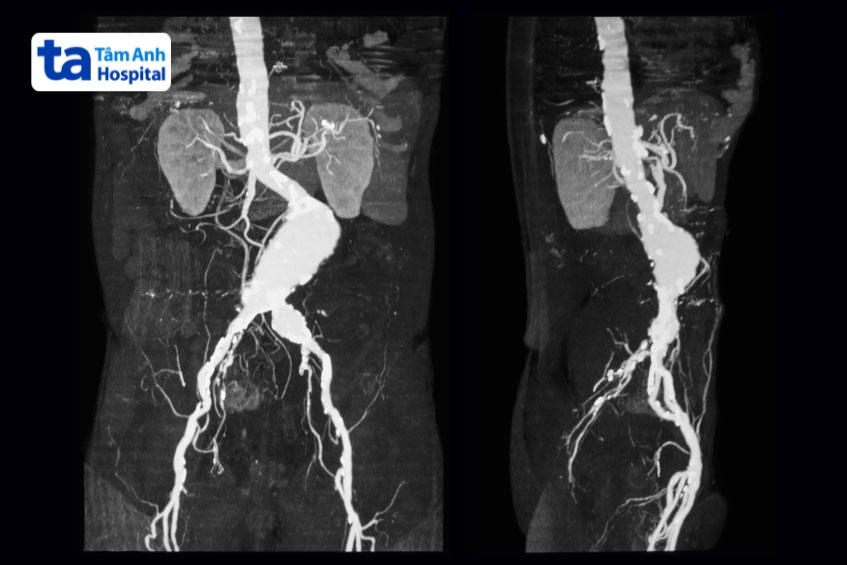

Phình động mạch chủ là một bệnh lý nguy hiểm, có thể đe dọa tính mạng nếu không được phát hiện và điều trị kịp thời. Động mạch chủ là mạch máu lớn nhất trong cơ thể, có nhiệm vụ mang máu giàu oxy từ tim đến các bộ phận khác. Khi thành động mạch chủ bị suy yếu, máu liên tục chảy qua sẽ tạo ra một khối phình, làm giảm chức năng vận chuyển máu và gây ra những biến chứng nghiêm trọng.

Một trong những biến chứng nguy hiểm của phình động mạch chủ là vỡ động mạch chủ. Đây là tình trạng cấp cứu đe doạ tính mạng vì khi động mạch bị vỡ, máu tràn ra ngoài có thể gây sốc mất máu nghiêm trọng, làm giảm lượng máu cung cấp cho các cơ quan quan trọng như tim, não, thận. Nếu không được can thiệp kịp thời, nguy cơ tử vong rất cao. Việc phát hiện sớm và điều trị phình động mạch chủ trước khi xảy ra biến chứng là yếu tố quan trọng để bảo vệ sức khỏe và nâng cao cơ hội phục hồi cho người bệnh. (1)